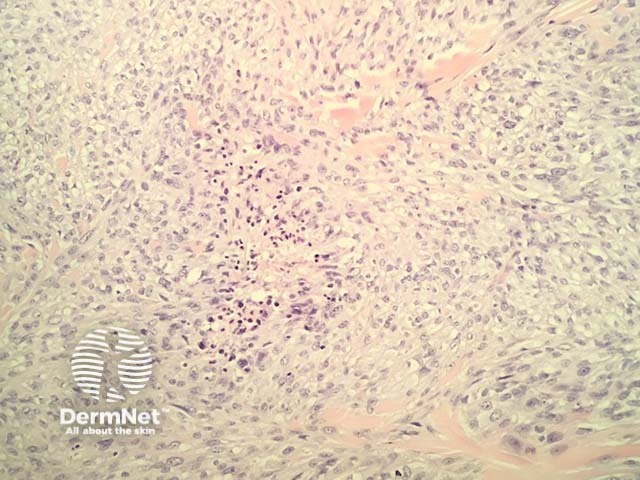

In mesothelioma, histopathology shows a diverse range of patterns: epithelioid, sarcomatous and biphasic (mixed). The majority of cases show a mixed pattern of epithelioid and spindled cells. In each of these subtypes the cells show marked nuclear atypia and invasion into surrounding structures. Metastasis to the skin usually shows a dermal tumour, often with overlying ulceration (figure 1). Higher power examination shows malignant cells with a variety of cell shapes ranging from tubulopapillary, spindled, clear cell, and small cell types. The example illustrated here is predominantly sarcomatous with a preponderance of spindled cells (figures 2-5). There are zones of necrosis (figures 3-5).

Figure 4